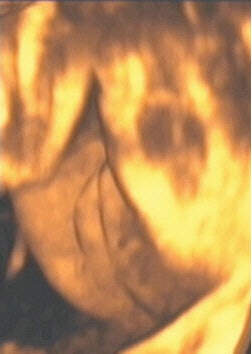

![]() |

| Figure 10, a 3-D ultrasound image of a fetus resting with its face against the placenta. Image courtesy of Stefano Ciatti, M.D. |